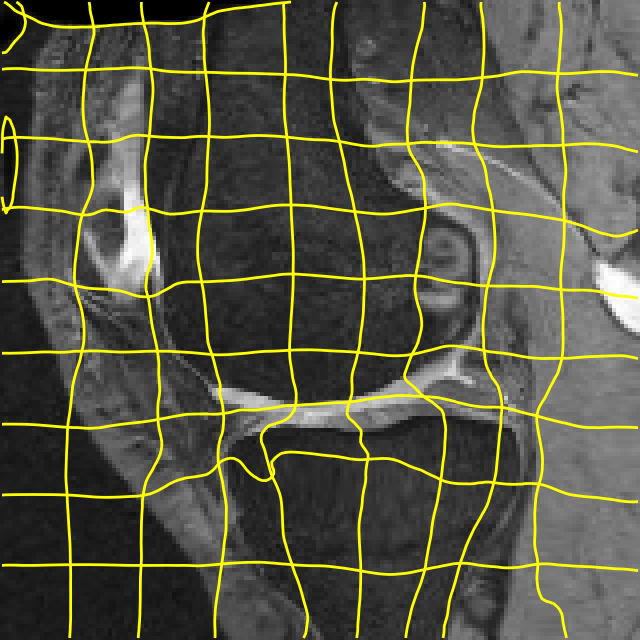

Moving

Target

Mono-0

Mono-5

DA-1

DA-5

Mono-200

Results: All trained networks are evaluated using Dice overlap scores between predictions and the manual segmentations for the segmentation network, or between the warped moving segmentations and the target segmentations for the registration network. Tabs. 1 and 2 show results for the knee and brain MRI experiments respectively in Dice scores (%). Fig. 2 shows examples of knee MRI registrations and brain MRI segmentations.

Qualitative results: DA achieves more anatomically consistent registrations than the mono-networks on the knee (Fig. 2) and Brain MRI samples (see supplementary material).